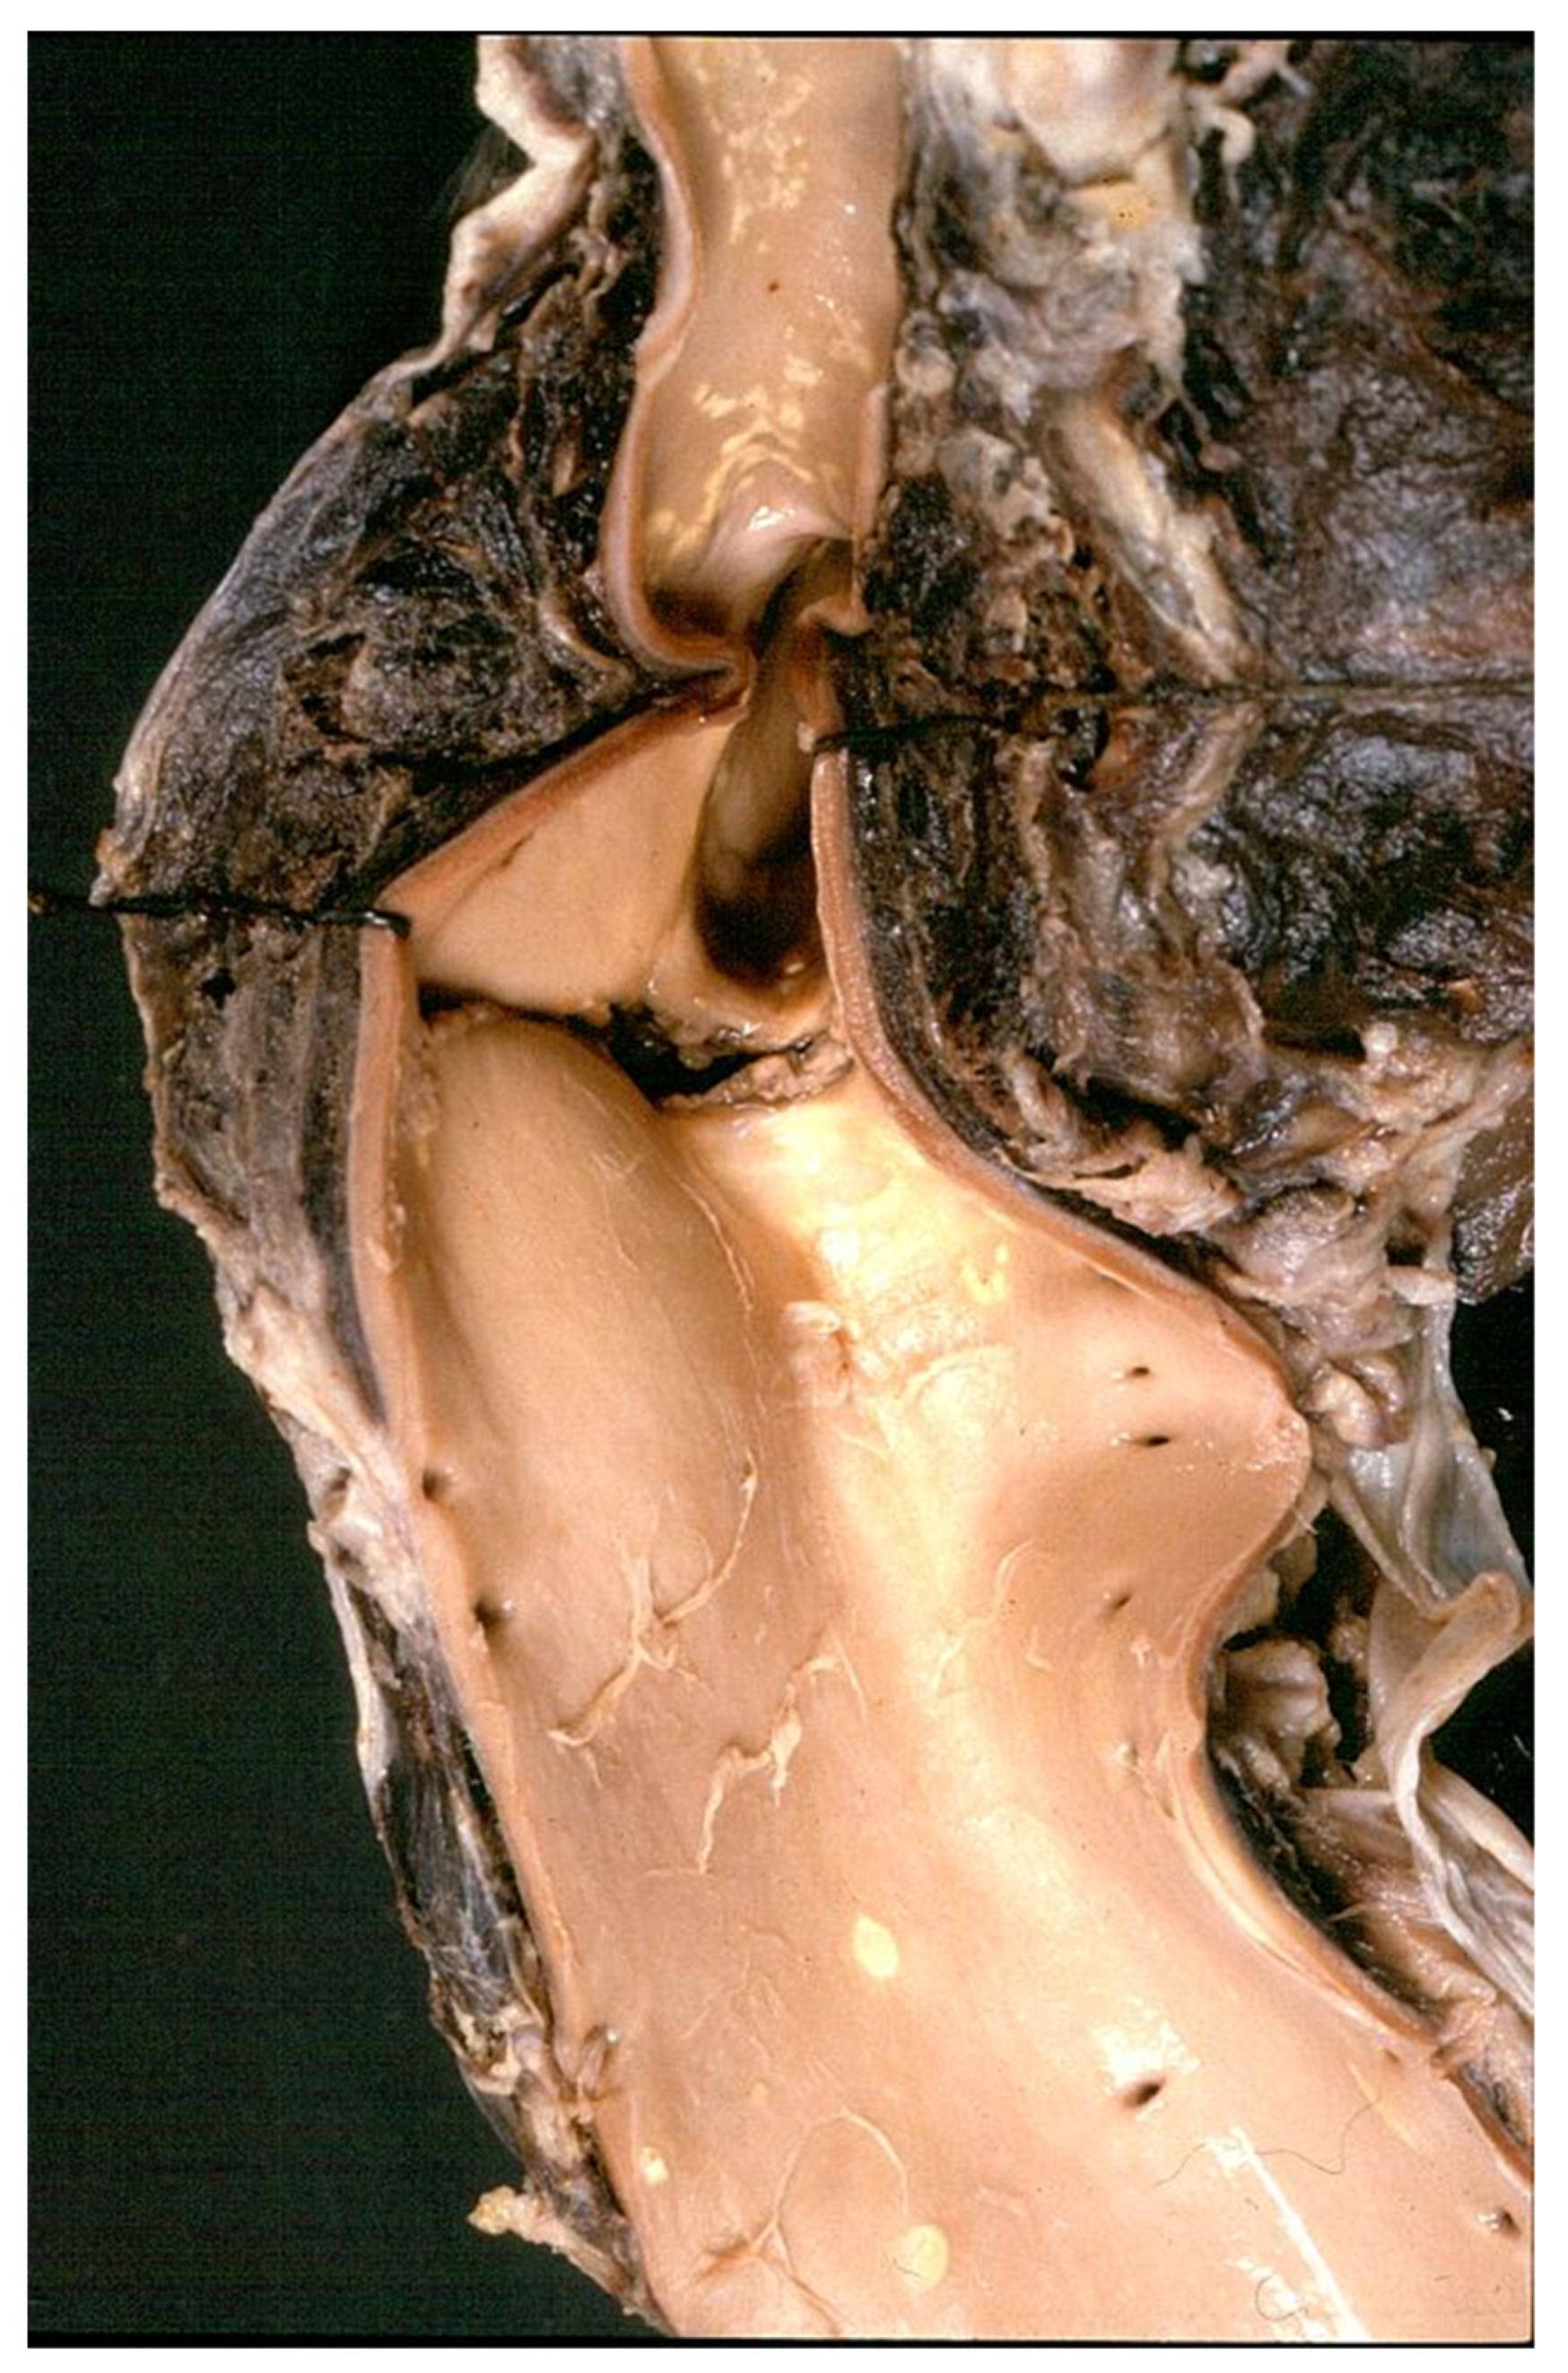

3.3. Degenerative Diseases of the Aorta